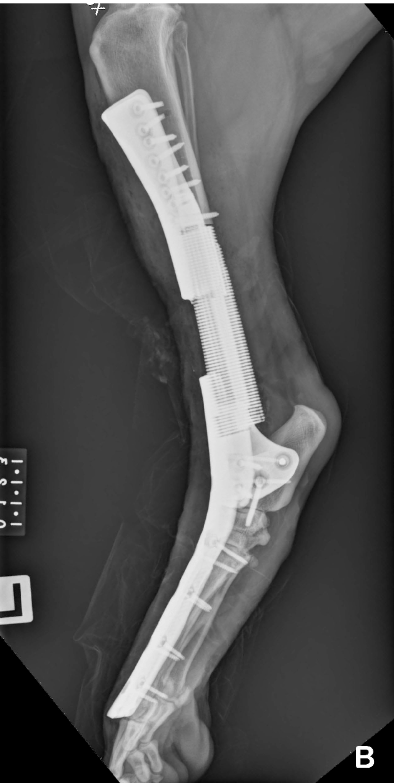

One day Zac limped around the corner, so we visited our local vet; unfortunately the vet determined that he had very early stages of Osteosarcoma an aggressive bone cancer. She advised us that due to the aggressive nature of the this cancer amputation was the usual treatment however Dr Johnathon Bray, at Massey University, was in the middle of a trial performing bone sparing operations, whereby the bone was removed and replaced with a custom designed titanium implant (Dr Bray moved to the UK in 2017).

We opted to check it out and investigations suggested Zac was a good candidate as the cancer was very early. The concerns were around him being the first tibia replacement (the second largest bone in their body, his back left leg) and he was a large dog.

The creation of the implant was specific to him whereby a CT scan provided an exact image for the vendor to print the titanium implant with a 3D printer. Because of the size of the implant it took them three goes before the vet was happy to proceed.

The operation was a success and treatment included four days of continual chemotherapy. When we picked up Zac he hobbled out and immediately jumped up placing his front legs onto a bench (his favourite position), fortunately the implant was well secured.